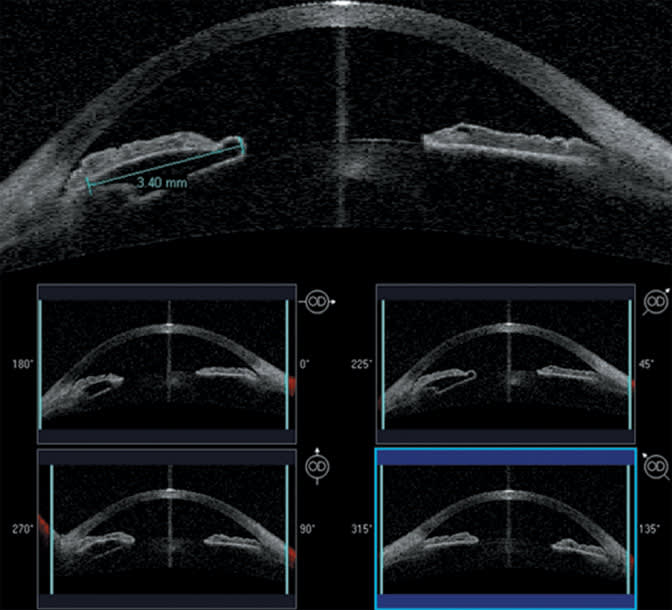

As the images on previous pages illustrate, surgeons performing corneal refractive procedures are finding the Visante OCT system an invaluable tool for surgical planning and post-op assessment. The same applies to phakic IOL implantation. The system can be used to ensure adequate space between intraocular structures, to document lens vault and choose the appropriate implant size.

The four-scan feature documents the extent and dimensions of an iris cyst.